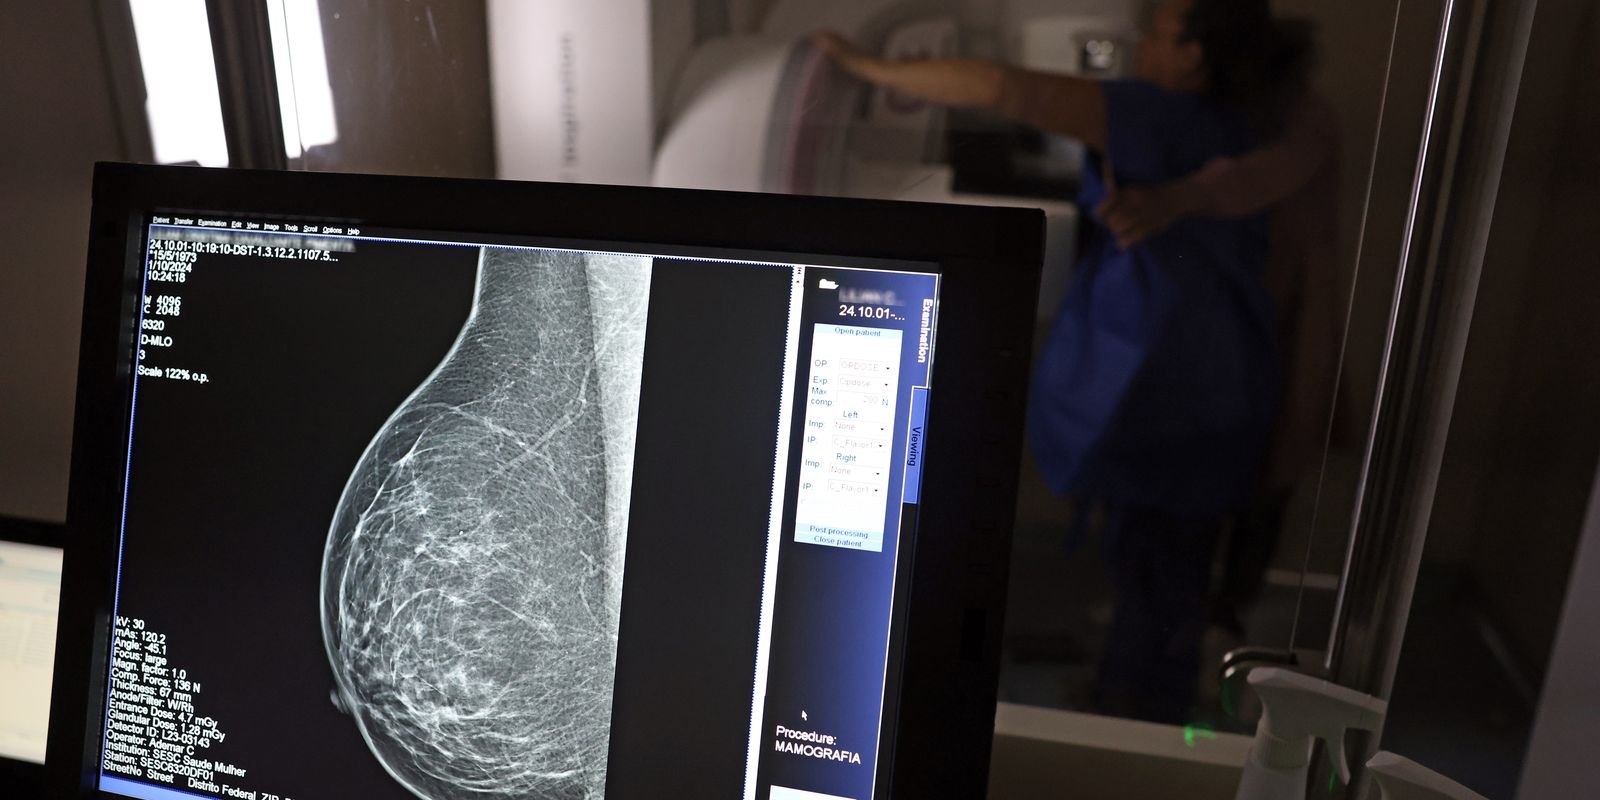

O caso levou os conselhos regionais de medicina de Minas Gerais e São Paulo a abrirem investigações tendo o médico como alvo. O Instituto Nacional do Câncer (Inca) também informou, à época, não haver evidência de que a mamografia possa causar câncer de mama e que, pelo contrário, o exame previne a doença.

O órgão anexou ao processo nota técnica do Ministério da Saúde segundo a qual “é recomendado que mulheres de 50 a 69 anos, de risco padrão, façam uma mamografia de rastreamento a cada dois anos. Esse exame pode ajudar a identificar o câncer antes de a pessoa ter sintomas”.